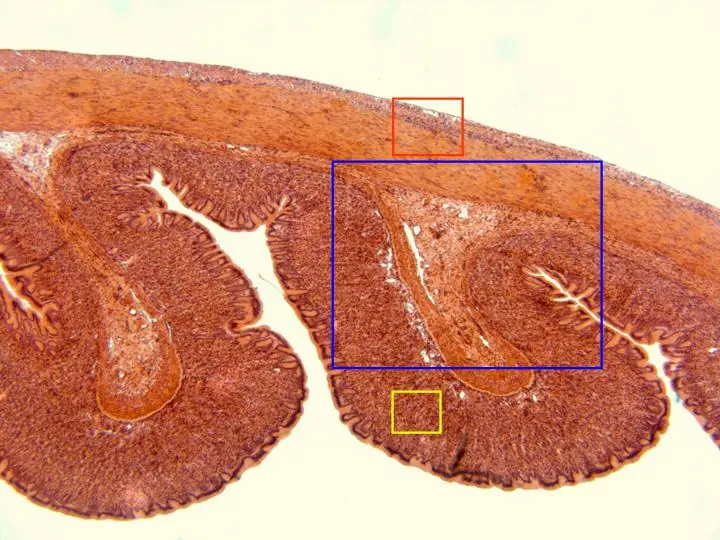

dijo:Reconstrucción fotográfica de parte de una sección de bazo, teñida con hematoxilina/eosina y observada con el objetivo de 10x. A este aumento se aprecia la cápsula formada por conjuntivo denso, de la cual parten trabéculas hacia el interior del órgano, además del parénquima esplénico. Éste lo integran dos zonas, denominadas pulpa blanca y pulpa roja, con un componente mayoritario linfocítico la primera y gran cantidad de eritrocitos la segunda. En otras microfotografías se ofrecen detalles a mayor aumento de algunas áreas (zonas encuadradas en azul y en rojo)

dijo:(Zona encuadrada en azul)Con el objetivo de 40x se observa un detalle de la superficie del órgano y parte de la pulpa del mismo. Son visibles la cápsula conjuntiva y una de las trabéculas que parten de ella, así como parte de la pulpa blanca y roja, más internamente localizadas. En otras microfotografías se aprecian detalles a mayor aumento de cada una de estas estructuras (zonas encuadradas en azul, rojo y amarillo)

dijo:(Azul) Con el objetivo de 100x se muestra el detalle de la cápsula esplénica, recubierta externamente por endotelio y en la que se distinguen núcleos de fibrocitos y abundante material fibrilar. Internamente a la cápsula se localiza parte del parénquima esplénico, pudiendo observarse uno de los sinusoides venosos

dijo:(Rojo) Con el objetivo de 100x se observa un detalle de una de las trabéculas, formada por tejido conjuntivo denso, distinguiéndose en ella, tanto fibras, como núcleos de las células integrantes. A ambos lados de la trabécula son visibles numerosos linfocitos, con sus núcleos teñidos de azul, formando parte de la pulpa blanca

dijo:(Amarillo) Con el objetivo de 100x se observa el detalle de uno de los sinusoides venosos que integran la pulpa roja. Se distingue algún núcleo del endotelio que lo reviste, así como los núcleos de células de la sangre en su interior. Alrededor aparece parte de la pulpa roja, siendo visibles numerosos hematíes

dijo:(Zona encuadrada en rojo)Con el objetivo de 40x se observa uno de los corpúsculos de Malpighi, en el cual se distingue la arteria central, rodeada del centro germinativo, con una marcada densidad de linfocitos y una zona marginal de transición con la pulpa roja a la izquierda, de menor densidad linfocítica. Más externamente se aprecia parte de la citada pulpa roja. En otra microfotografía se observa un detalle a mayor aumento de la parte central del corpúsculo (rojo)

dijo:Con el objetivo de 100x se observa el detalle de uno de los corpúsculos de Malpighi, en el cual se distingue la pared de la arteria central, rodeada del centro germinativo, con una marcada densidad de linfocitos